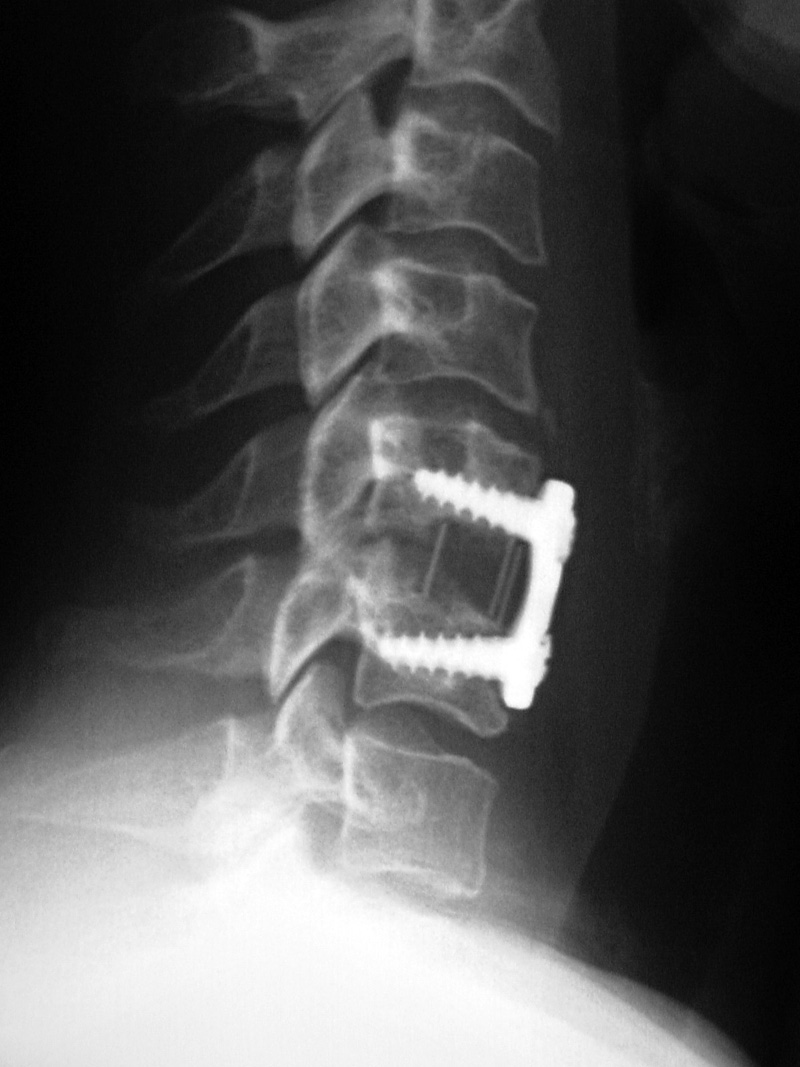

Anterior cervical disk fusion (ACDF) and PEEK cage at C5-6 |

Cervical spine intervertebral disk fusion cage |